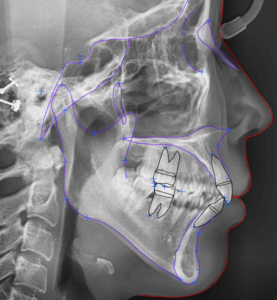

MARPE 악궁 확장을 통한 안면 골격 비대칭, 횡적 부조화(transverse discrepancy) 개선 과정

오늘은 진단이 다소 어려운 케이스인 '횡적 부조화'에 대한 내용을 설명해보려 합니다. ​ 전문적인 내용이라 살짝 이해하기 어려우실수도 있겠지만.. ​ 실제 케이스와 함께 최대한 쉽게 풀어서 설명드리도록 하겠습니다. 『불편하고 어딘가 불안정한…